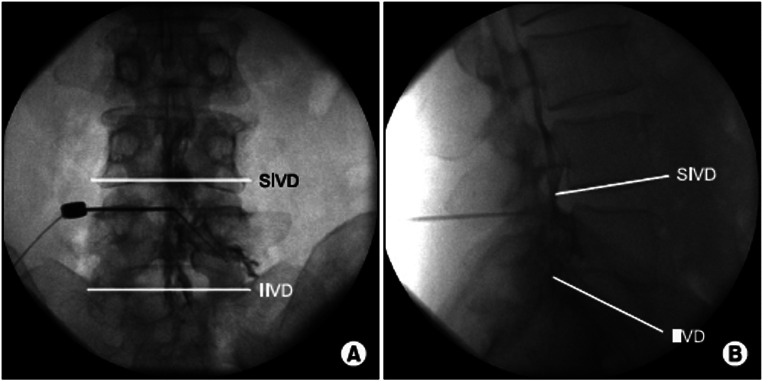

AP (A) and lateral (B) fluoroscopic views during interlaminar epidural steroid injection showing contrast localized to the epidural space.

• The ventral interlaminar line (VILL) connects the anterior margins of consecutive laminae and represents the earliest expected location of loss of resistance

• CLO provides better needle tip visualization, more consistent epidural space identification, and ability to redirect after a false LOR compared to lateral view

• If the needle advances 1-2 mm past the VILL without LOR, check additional views and inject a small amount of contrast to confirm position